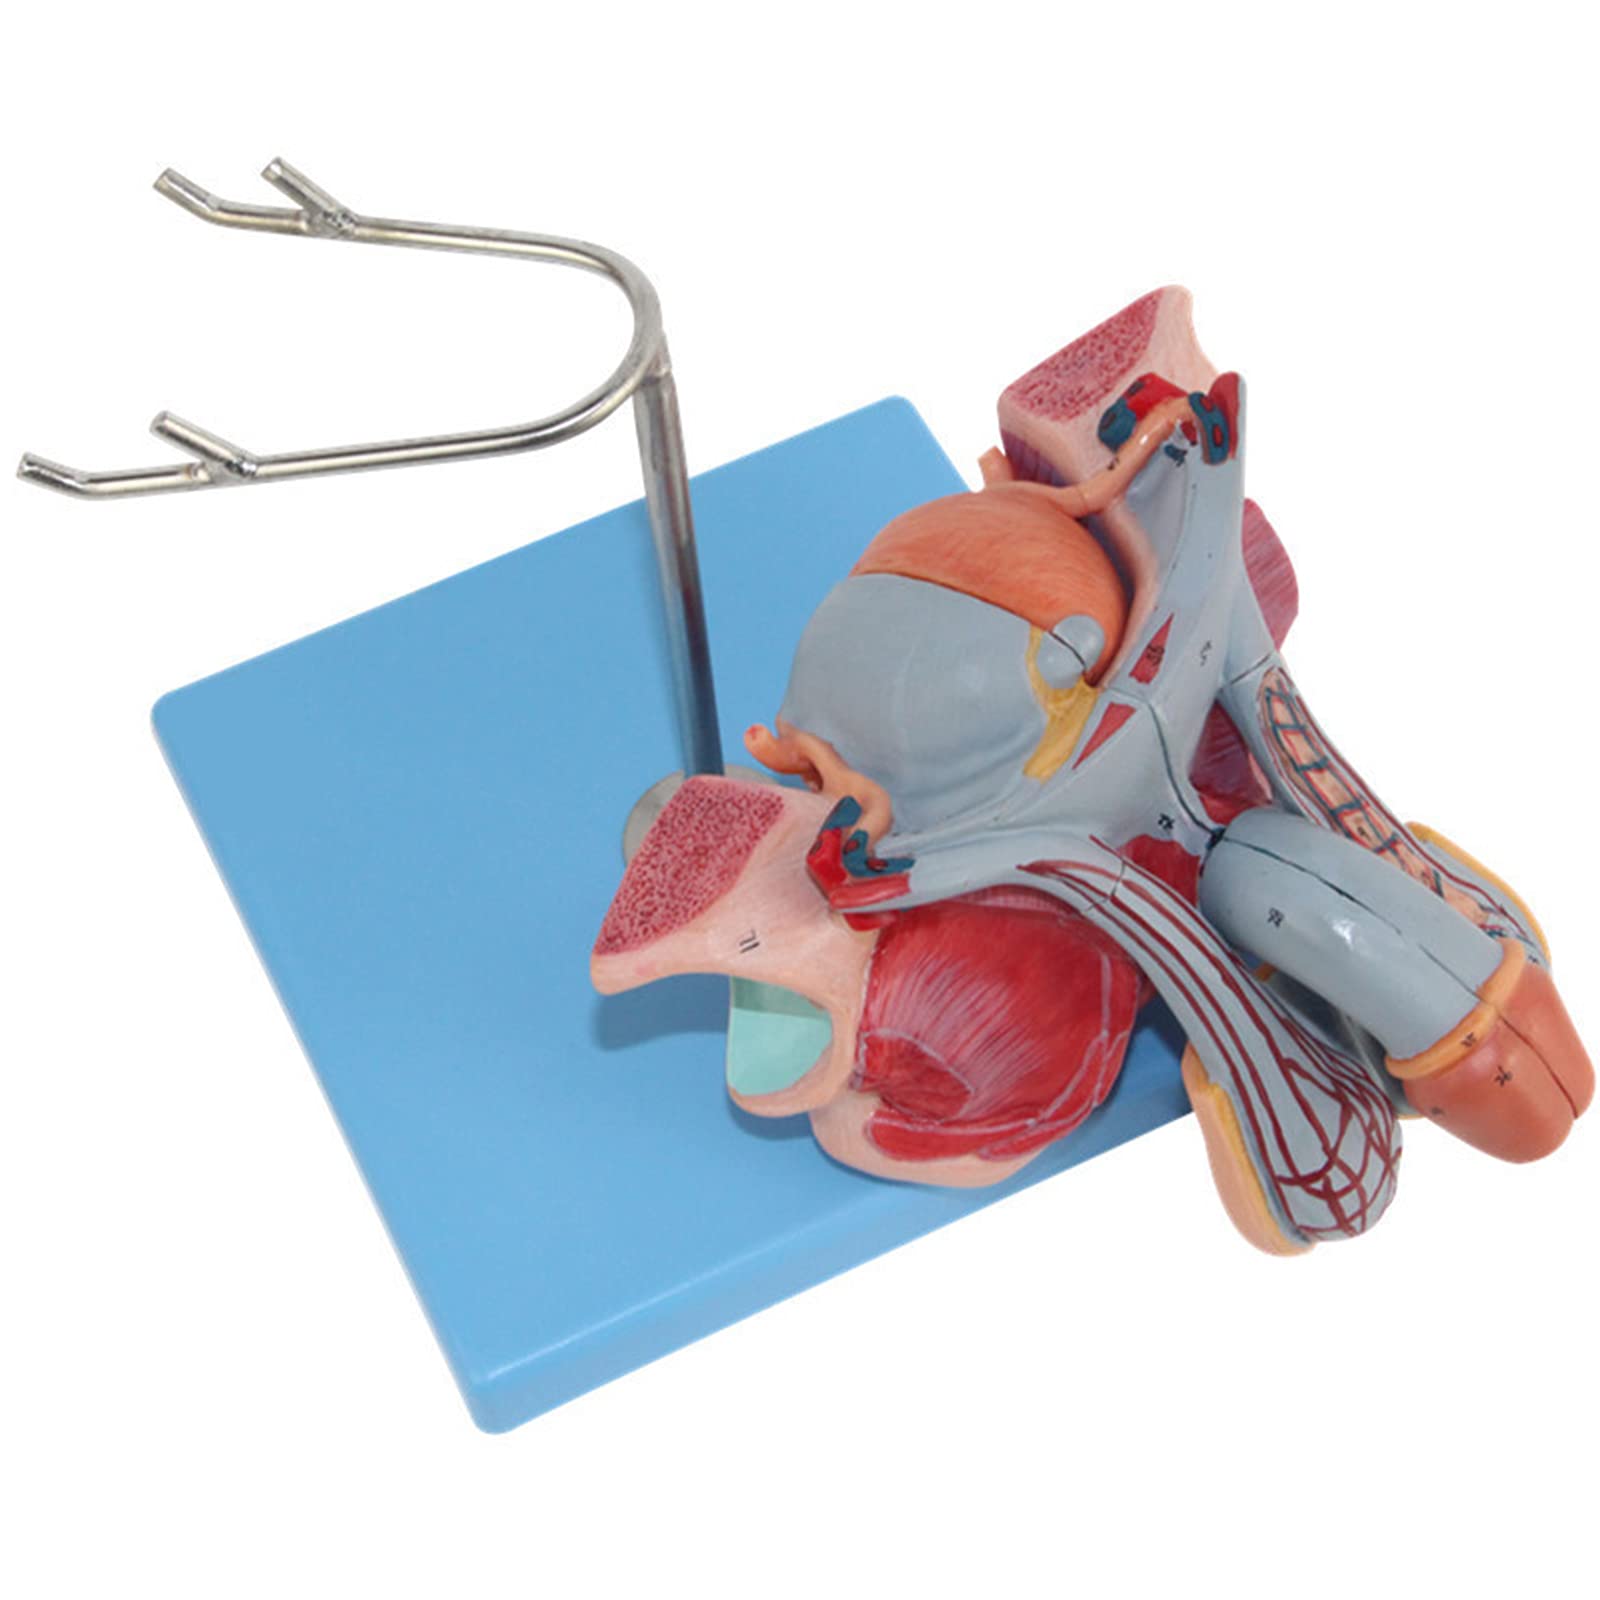

The Male Reproductive Model is a meticulously crafted anatomical aid featuring five detailed parts, including male genital organs and bladder sections. Made from durable, eco-friendly PVC, this model is designed for educational excellence, making it an ideal tool for schools and hospitals to enhance understanding of human anatomy.